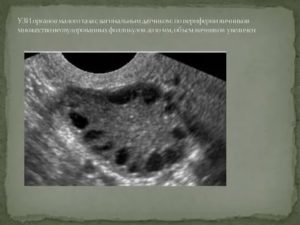

Увидеть это можно с помощью УЗИ:

• На периферии яичника на 5 день после завершения месячных можно увидеть до 10 антральных фолликулов. Их размер от 2 до 4 мм.

• к 7 дню их размер увеличивается до 6 мм, поэтому можно разглядеть капиллярную сетку на них.

• К 9-10 дню выявляются доминантные фолликулы. Именно они продолжают свое дальнейшее развитие, увеличиваясь в размере. 14-15 мм – это нормальный его размер, остальные будут в замороженном состоянии

• К 14 дню доминантный фолликул разовьётся до 25 мм, активно вырабатывая женский гормон эстроген. В этот момент с помощью УЗИ можно точно рассчитать день овуляции.

УЗИ необходимо для определения количества фолликул после месячных и в первые дни цикла. Согласно полученной информации, можно сделать вывод о продолжительности фертильного периода.

В этот период фолликулы достигаю размеров, достаточных для определения их количества с помощью ультразвукового исследования.